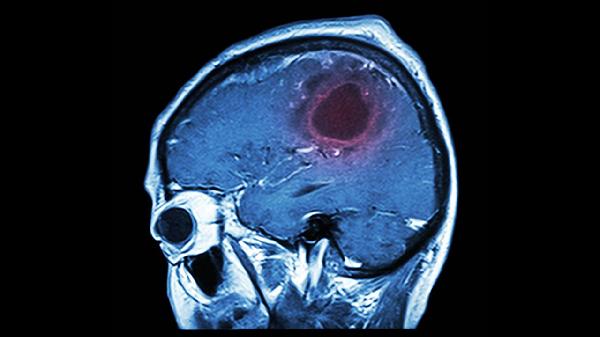

大腦就像一臺精密儀器,需要細心呵護才能保持最.佳狀態。但生活中一些看似不起眼的習慣,卻可能在不知不覺中給大腦帶來巨大傷害。腦溢血等嚴重問題往往不是突然發生的,而是日積月累的結果。瞭解這些潛在危險,及時調整生活方式,才能更好地保護我們的大腦。

大腦在睡眠時會進行自我修復和清理代謝廢物。長期熬夜會干擾這個過程,導致大腦積累有害物質,增加腦血管負擔。研究發現,長期睡眠不足的人更容易出現腦血管問題。

夜間本該是血壓下降的時間段,熬夜卻讓身體保持興奮狀態。這種不規律的血壓變化會給血管壁帶來額外壓力,長期如此可能增加血管破裂風險。

人在憤怒時血壓會迅速升高,這種突然的壓力變化對腦血管衝擊很大。頻繁的情緒波動就像一次次”微型地震”,逐漸削弱血管的承受能力。

持續的壓力狀態會刺激身體分泌更多壓力激素,這些物質會加速血管老化,使血管壁變得脆弱。學會調節情緒,保持心態平和對大腦健康至關重要。